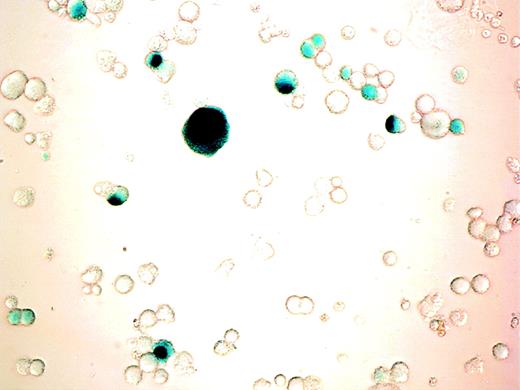

β-gal expression in cultured cells after adenoviral transduction. CD34+ cells were cultured with PEG-rHuMGDF for 10 days before incubation with AdCNLacZ (MOI of 200). β-gal expression was visualized by light microscopy after cell fixation and X-gal staining as described in Materials and Methods. Photomicrograph of adenovirus infected cells (400×). Note the blue nuclear staining of successfully transduced cells. No blue coloration was detectable in any cell from samples that were similarly stained but were incubated with virus control.